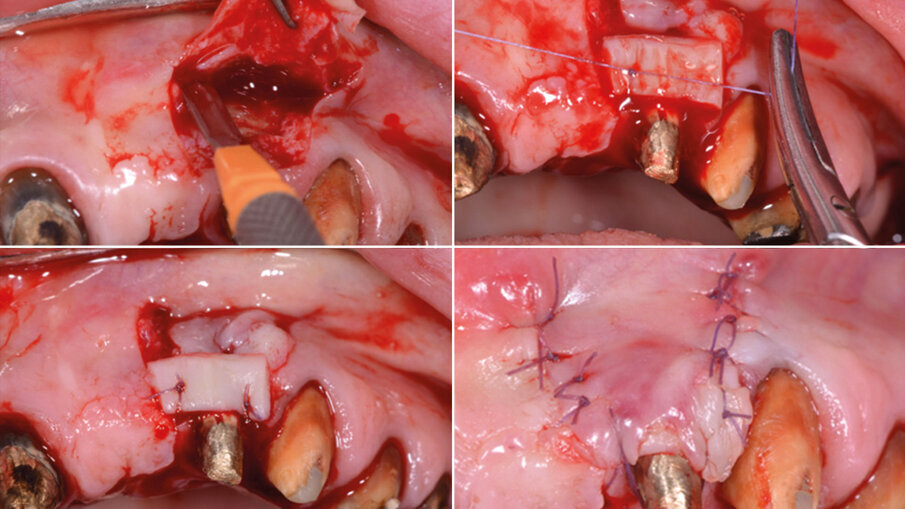

La riabilitazione protesica inizia con la rimozione del vecchio circolare superiore e nella ripreparazione dei monconi con sostituzione delle porzioni demineralizzate, consecutiva alla ribasatura e rifinitura dei provvisori pre limatura (Fig. 4).Per risolvere il problema estetico di mancanza di gengiva aderente attorno all’elemento 22, effettuiamo un lembo bilaminare con innesto di tessuto connettivo. Utilizzando per lo scollamento a tutto spessore nella parte centrale della recessione un inserto piezo surgery mectron apposito, solleviamo delicatamente il nostro lembo e continuiamo lo scollamento a mezzo spessore intorno al letto di innesto con bisturi (Fig. 5). Successivamente posizioniamo l’innesto di connettivo prelevato dal palato, privato della porzione epiteliale, e suturiamo con punti di sutura staccati in 7.0 sul letto ricevente (Fig. 6).

Fig. 5 - Lembo e scollamento con inserto piezo.

Fig. 6 - Innesto e sutura del lembo.

Sulle suture viene applicato l’olio di oliva evo ozonizzato attivato Perioral 3 (Gemavip), che unisce l’efficacia terapeutica dell’olio di oliva alle molecole attive dell’ozono. Grazie a questo processo il prodotto vanta proprietà batteriche, fungicide e antinfiammatorie che svolgono un’azione mirata sulla riparazione epiteliale. Il cetylpyridinium svolge un’azione antisettica e battericida, la clorfenesina è un antimicotico e un miorilassante. Il collagene a basso peso molecolare è facilmente assorbibile e lavora per la rigenerazione cellulare. L’acido ialuronico a basso e alto peso molecolare coadiuva la rigenerazione cellulare. Viene dato alla paziente un bite anteriore di svincolo per riposizionare la mandibola e dopo una settimana viene registrata la posizione delle arcate. Vengono posizionati i nuovi provvisori con le nuove registrazioni occlusali. Nel frattempo vengono inseriti 4 impianti in zona 35, 36, 46 (post estrattivo a carico ritardato con rigenerazione guidata GBR) e in zona 26 a carico ritardato, mentre era già presente un impianto in zona 34 che presentava un minus cervicale con estetica carente (Fig. 7).